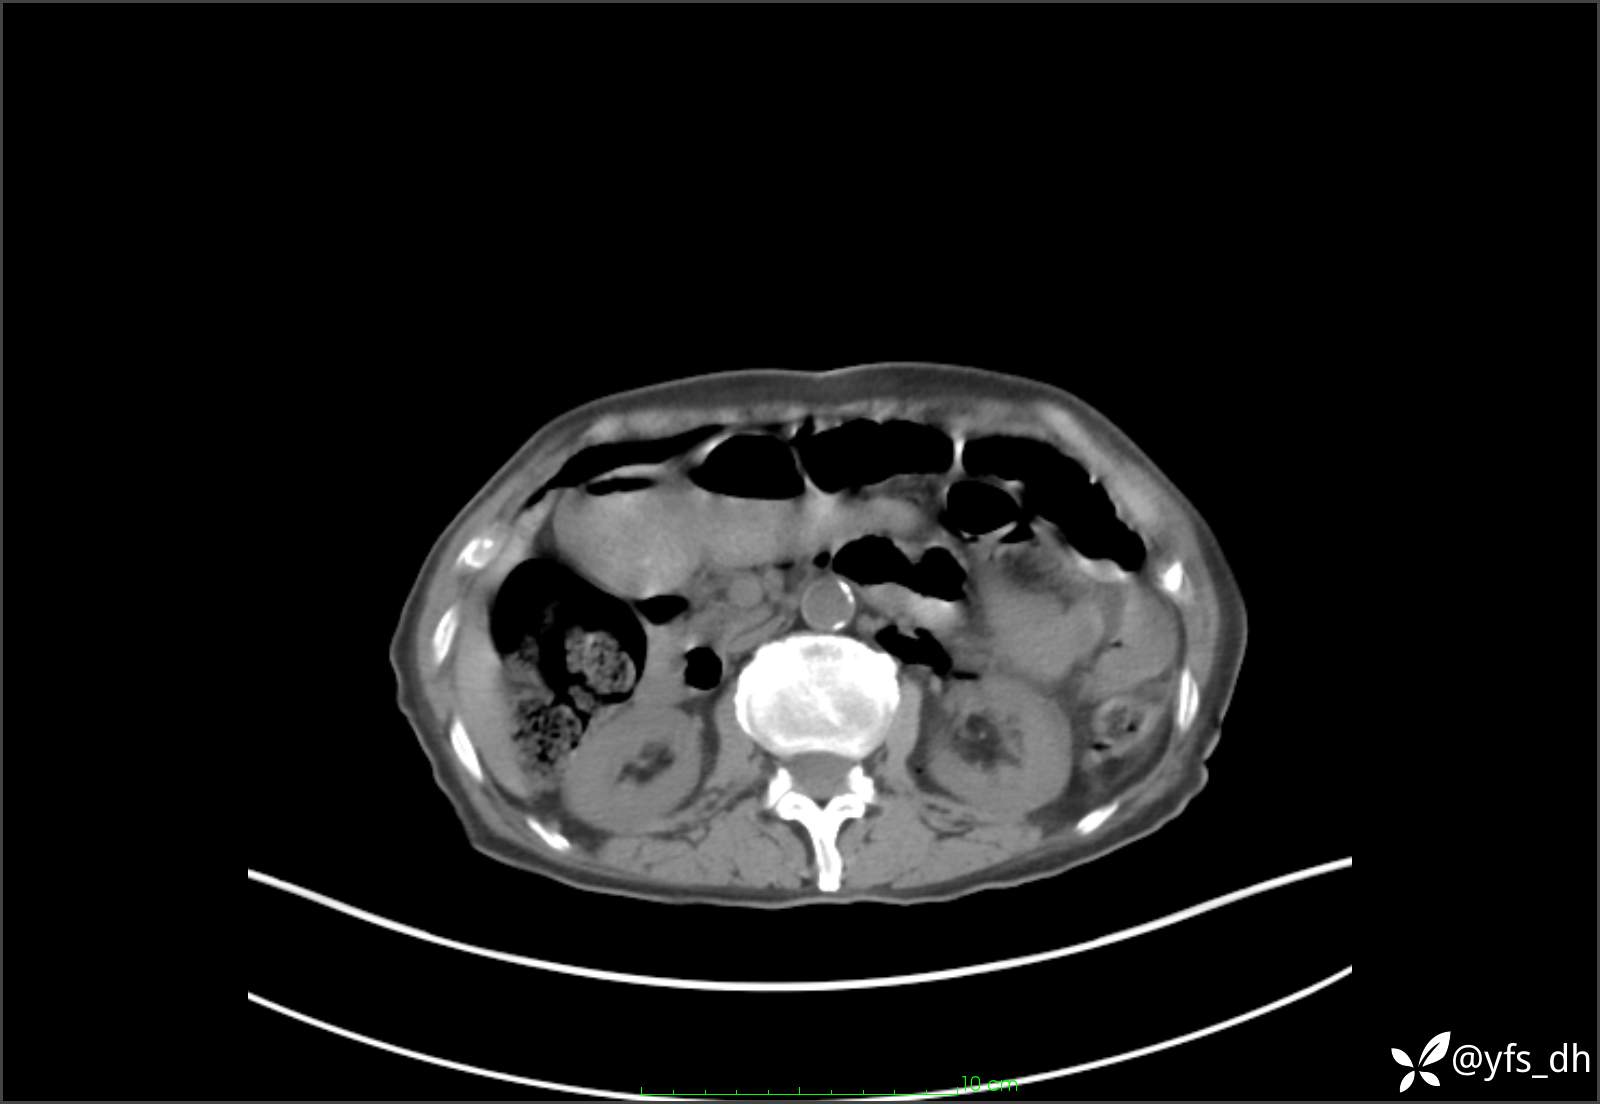

1.简要病史:患者4天前突发上腹部疼痛不适,但可以忍受。3小时前饭后突然加重,不能忍受后就诊。

2.简要手术记录:术中见腹盆腔大量肠液及粪便,乙状结肠中下段见一约3cm的破口。